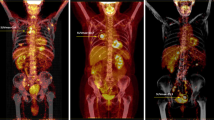

Patient background factors and Fuhrman grades of the 31 cRCCs in 31 patients are summarized in Table 1. No significant difference was found in patient age (P = 0.69) or gender (P = 0.95) between the high- and low-grade tumours. Of the 31 patients, two had a Fuhrman grade 1 tumour, 15 had a grade 2, 13 had a grade 3, and one had a grade 4 tumour. PET/CT images of Fuhrman grade 2 and 3 cRCCs are illustrated in Figs. 1 and 2, respectively. The maximum cRCC diameter ranged from 26 to 152 mm, with a mean size of 67.4 ± 32.3 mm. The maximum diameter of the high-grade tumours (range 35–152 mm, mean 79.7 ± 31.0 mm) was greater than that of the low-grade tumours (range 26–129 mm, mean 57.2 ± 30.4 mm) (P = 0.02) (Fig. 3).

Correlation between SUV and pathological grade

18-F FDG-PET/CT is a functional imaging modality for the detection of various malignant tumours on the basis of increased glucose uptake. Although the first indication of 18-F FDG-PET/CT for the detection of RCC was reported by Wahl et al. [26] in 1991, this technique is not commonly used for the detection of RCC, given the fact that the kidney is the major excretion route for 18-F FDG. Previous studies have demonstrated low sensitivity of 18-F FDG-PET/CT for the detection and diagnosis of RCC [27, 28]. Another clinical application of 18-F FDG-PET/CT is in estimating the biological grade of malignant tumours. Some studies have shown that increased uptake of 18 F-FDG is observed more frequently in malignant tumours with higher pathological grades [29, 30].